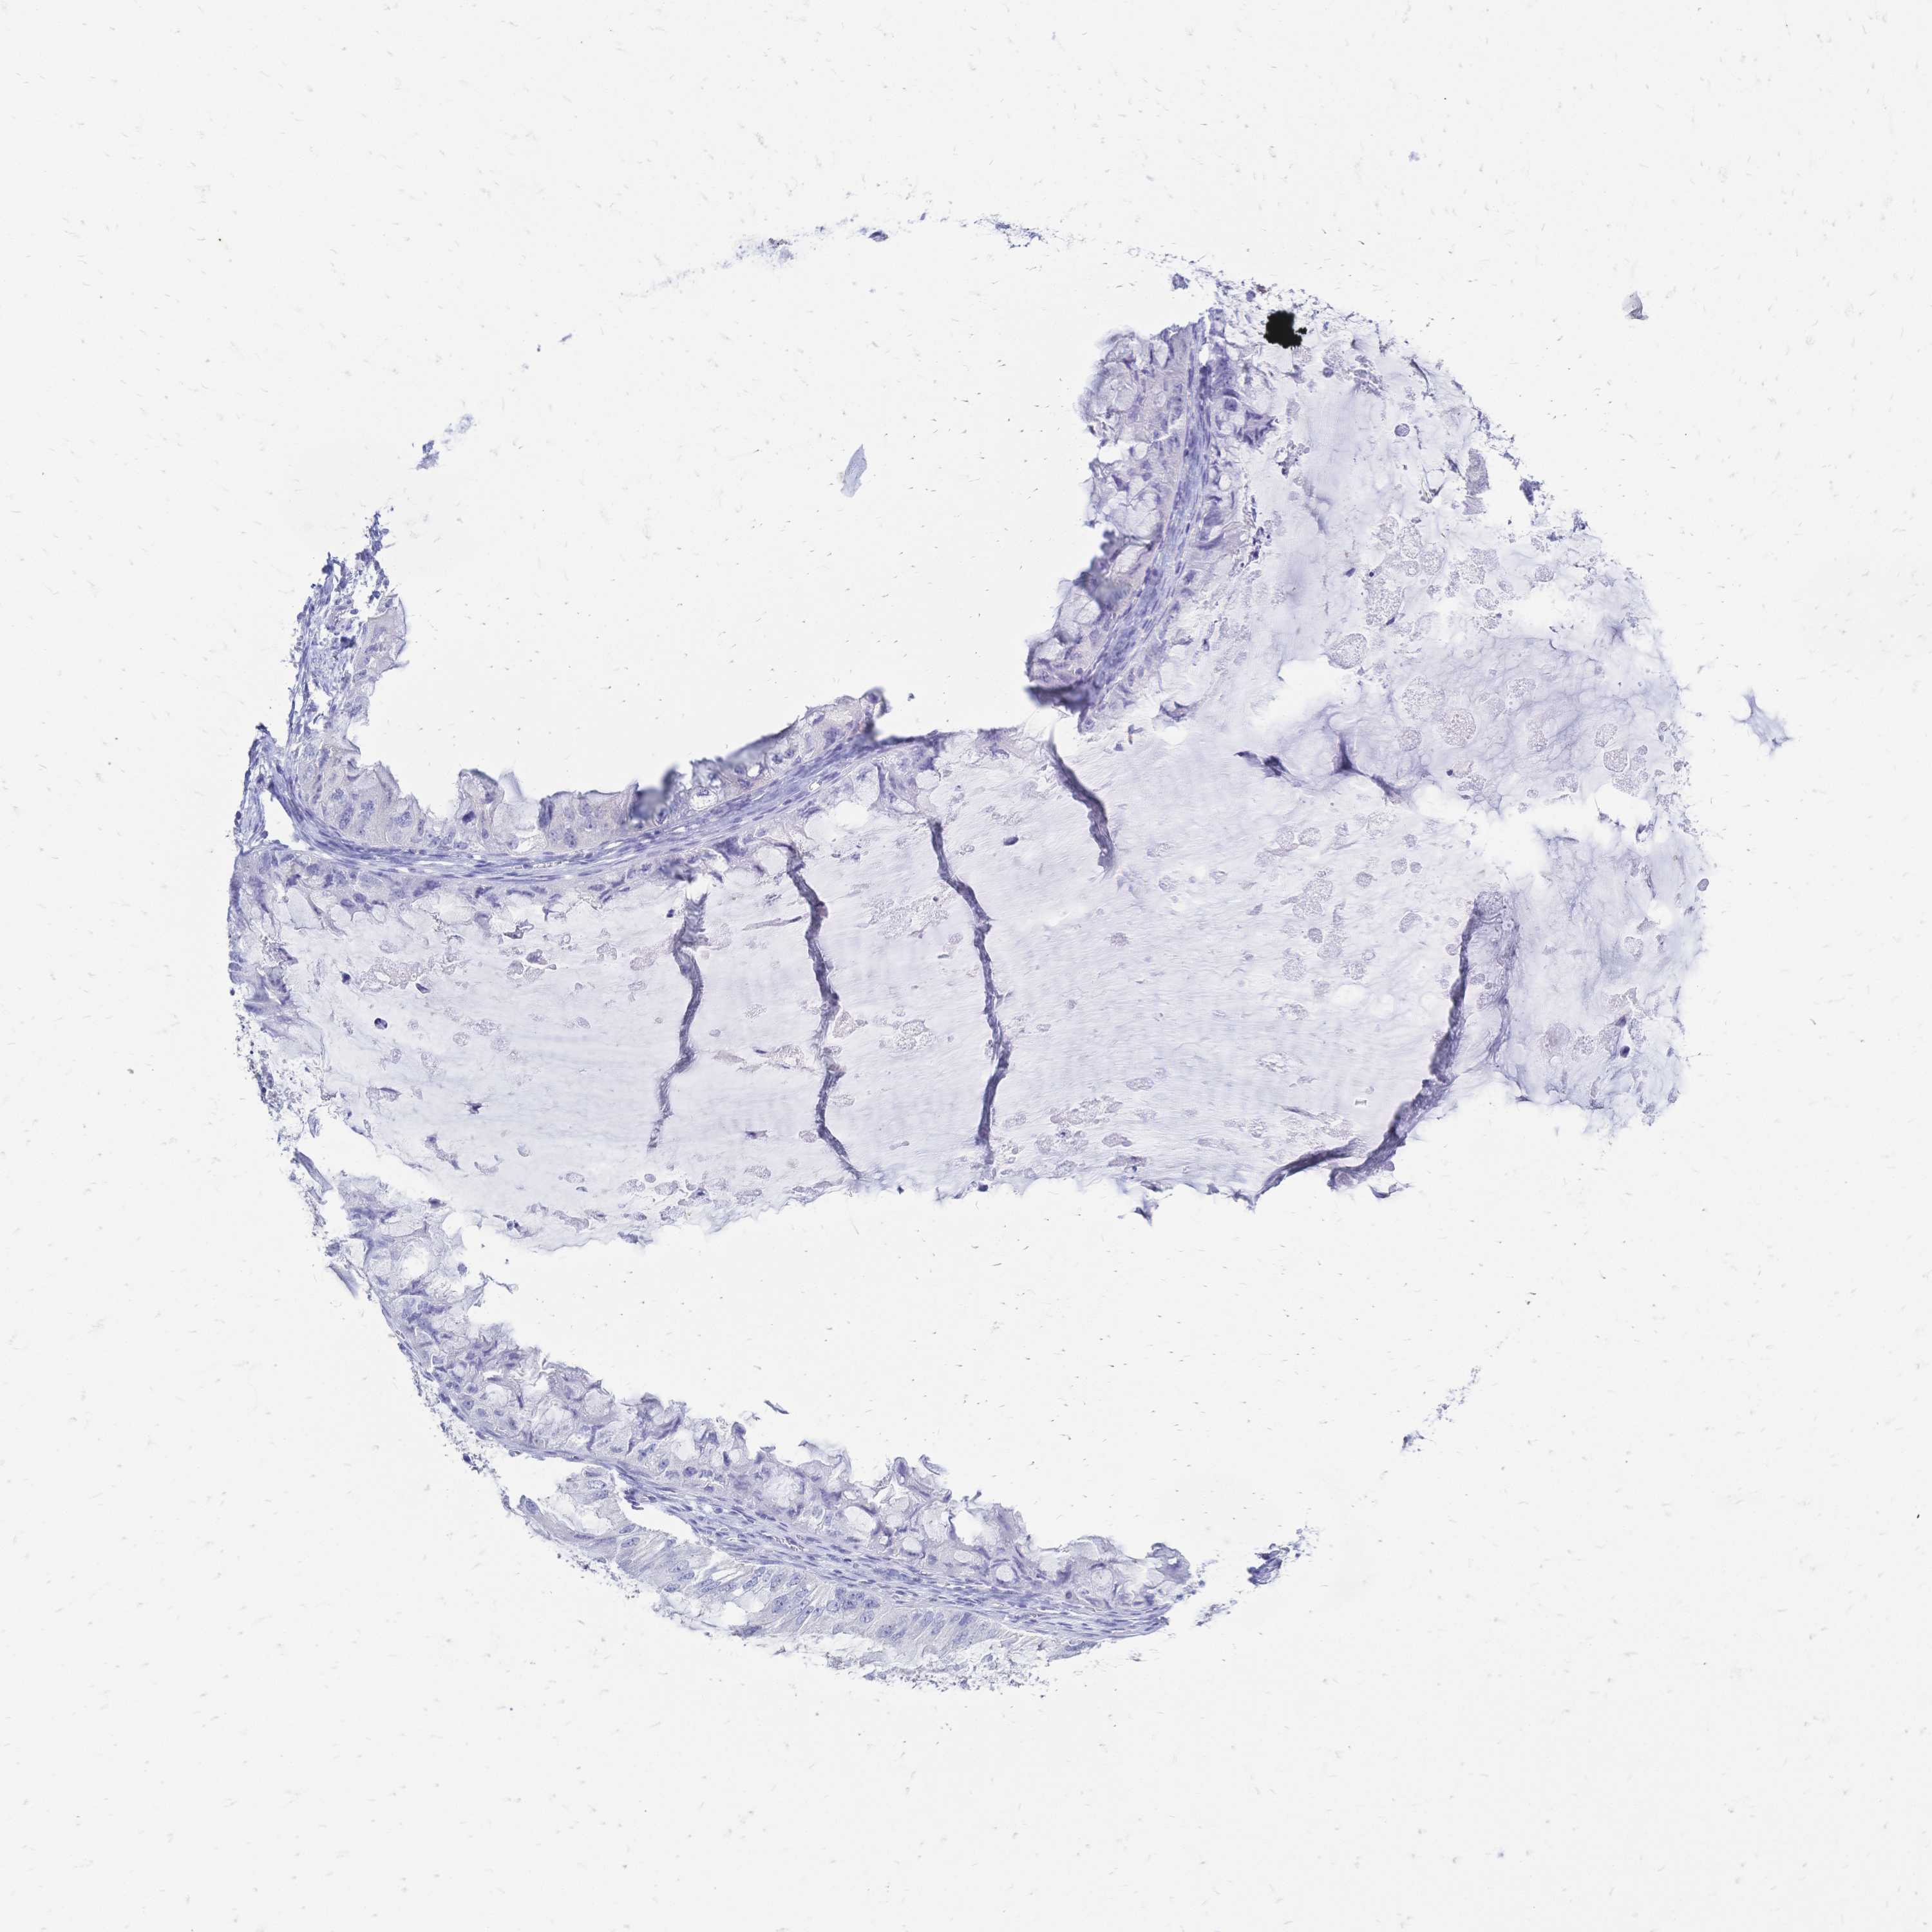

OVARIAN CANCER - Protein expressioni

A mouse-over function shows sample information and annotation data. Click on an image to view it in a full screen mode. Samples can be filtered based on level of antibody staining by selecting one or several of the following categories: high, medium, low and not detected. The assay and annotation is described here.

Note that samples used for immunohistochemistry by the Human Protein Atlas do not correspond to samples in the TCGA dataset.

Antibody stainingi

Antibody staining in the annotated cell types in the current human tissue is reported as not detected, low, medium, or high, based on conventional immunohistochemistry profiling in selected tissues. This score is based on the combination of the staining intensity and fraction of stained cells.

Each image is clickable and will lead to virtual microscopy that enables deeper exploration of all samples and also displays staining intensity scores, fraction scores and subcellular localization as well as patient and tissue information for each sample.

Antibody HPA056614

Staining

High

Medium

Low

Not detected

Intensity

Strong

Moderate

Weak

Negative

Quantity

>75%

75%-25%

<25%

None

Location

Nuclear

Cytoplasmic/membranous

Cytoplasmic/membranous,nuclear

Cystadenocarcinoma, serous, NOS

Cystadenocarcinoma, mucinous, NOS

Carcinoma, endometroid